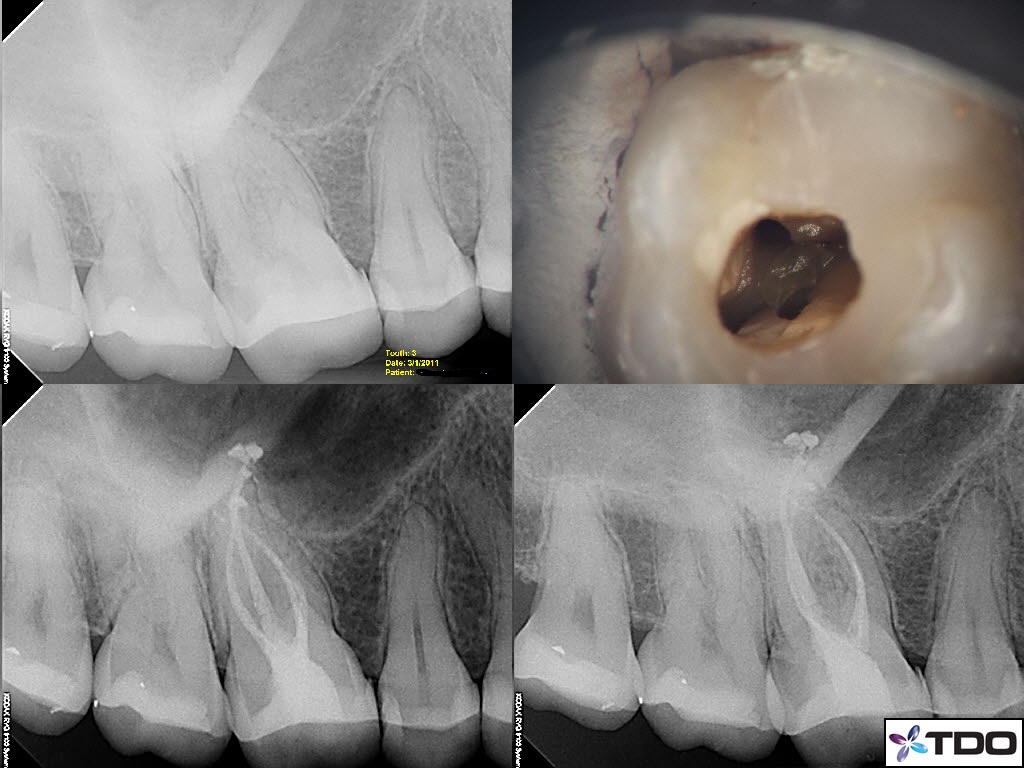

From tdouniversity.tdo4endo.com

Pulp stones TDO University What Causes Dental Pulp Stones Nearly every characteristic that leads us to describe them ends up in a range. pulp stones are one of the most entropic entities in the dental world. located within the central pulp cavity or the root canal, these dental pulp stones are extremely narrow and cause a. calcification can occur in the dental pulp as discrete calcified. What Causes Dental Pulp Stones.